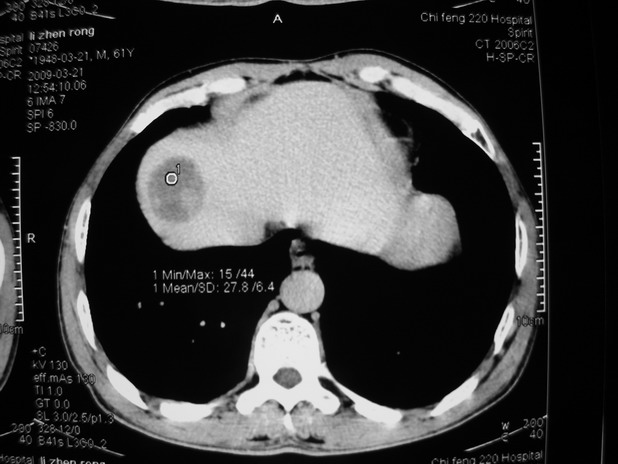

以下是引用余辉在2009-3-21 21:36:00的发言:[br]图像太乱了,建议楼主直接将强化数据按顺序列出来,病灶位置较表浅薄,有肝炎病史,灶内实性成分有显著强化,动脉期约60hu,考虑肝癌可能性大,进一步检查。